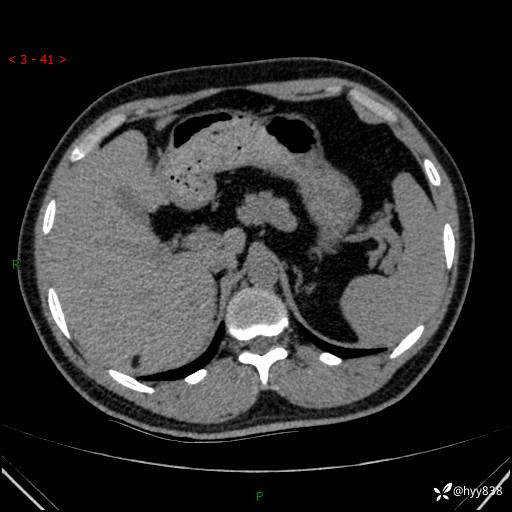

患者性别:男

患者年龄:28岁

简要病史:右肾肿瘤术后,常规复查

辅助检查:CT

临床诊断:右肾肿瘤术后

腹部CT+颅脑CT平扫